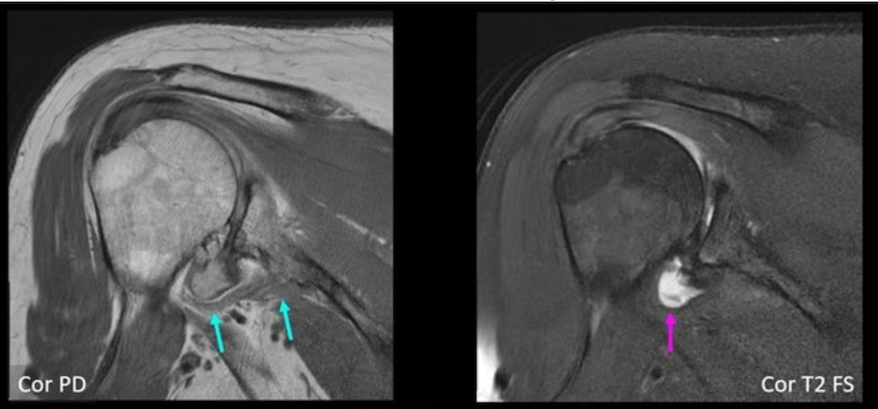

L’exploration de toutes les IRM de son institution a révélé au Dr Padwal et ses collègues la présence d’un TMFI documenté chez 100 patients (76 hommes, 24 femmes ; âge moyen, 58,6 ans). A titre de comparaison, un échantillon respectif de 100 IRM d'épaule chez des patients sans TMFI (53 hommes, 47 femmes ; âge moyen 56,4 ans) a été obtenu. Tous les examens ont été évalués par consensus par deux radiologues (un spécialiste musculo-squelettique avec 25 ans d'expérience, ainsi qu'un résident en radiologie de 4e année) pour un AIGM avec confiance diagnostique, notant l'origine et l'insertion musculaires.

De plus, au sein de la cohorte TMFI, de nombreux AIGM se placent en regard du nerf axillaire avec une neuropathie axillaire concomitante. Chez les patients atteints de TMFI en effet, la distance entre l'AIGM et le nerf axillaire a été mesurée, documentant tout signal nerveux axillaire anormal. Le TMFI a ensuite été classé selon la classification de Goutallier, tandis que la présence d'une atrophie et/ou d'un œdème a été notée.

L'AIGM a été observé chez 89/100 patients atteints de TMFI ; 30/100 chez les patients sans TMFI. Dans tous les cas, l’AIGM provenait du col glénoïde inférieur et était inséré sur le col huméral/diaphyse humérale proximale. La marge inférieure de l'AIGM chez les patients atteints de TMFI touchait le nerf axillaire chez 39 patients (46 %), avec un signal anormal chez 23 d’entre eux (27 %).